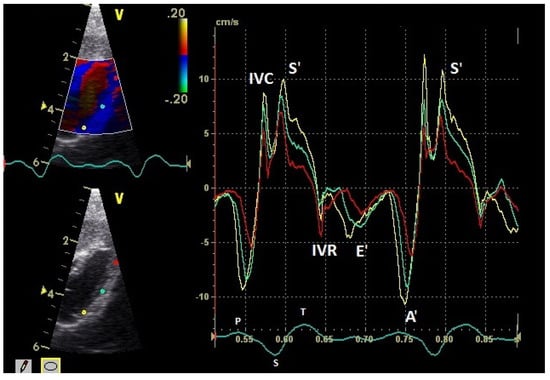

Figure 3.

Basal myocardial velocities in the four-chamber view measured by TDI: sample areas (Ø 2 mm): red: right ventricular free wall; yellow: left ventricular free wall; green: septum; early diastolic: E’ wave; late diastolic: A’ wave; systolic tissue velocities: S’ wave. Isovolumetric contraction: IVC; isovolumetric relaxation: IVR; HR: heart rate. Electrocardiogram: P: P wave; S: S wave; T: T wave.

The positive S’ wave of the TDI curve (Figure 3 and Figure 4; ascending part of the S wave to the descending part of the T wave of the ECG) describes the systolic movement of the heart base toward the heart apex and represents the expulsion phase of the heart. In the middle of the S’ wave of the TDI, there is little movement of the heart apex toward the heart base and the myocardial velocities are negative (Figure 2). This movement in the middle part of the systole led to an irregular shape of the S’ wave in the TDI curve (Figure 3). The negative E’ wave (Figure 3 and Figure 4; after the T wave of the ECG) in the TDI curve describes the movement of the myocardium during the passive ventricular filling and the second negative A’ wave of the TDI curve (Figure 3 and Figure 4; P wave of the ECG) describes the movement of the myocardium in the active filling phases of the heart during the diastole away from the heart apex. Before and after the S’ wave, the TDI curve showed undirected deflections as a sign of isovolumetric contraction (IVC) and relaxation (IVR; Figure 3 and Figure 4). However, the transition between the A’ and S’ waves (IVC) and the S’ and E’ waves (IVR) could be flowing and sometimes difficult to see.

The systolic and diastolic peak tissue velocities depending on the myocardial segment are shown in Table 1. In general, the highest myocardial velocities are visible at the atrioventricular valvular annulus in the basal segments. The velocities decrease significantly and continuously to the apex of the heart for the S’, E’, and A’ waves (p ≤ 0.001). Significant differences in the myocardial velocities could also be detected between the heart septum and the left and right free wall (Table 1).

In the examined pigeons, the systolic velocities (S’ wave) of the left and right free wall were significantly higher (p ≤ 0.001; Table 1) than the S’ wave velocities of the heart septum. The S’ wave velocities of the right free wall were not significantly different to the velocities of the left free wall.

The diastolic E’ wave velocities (passive diastolic filling) of the left and right free wall were significantly higher than in the septum (p ≤ 0.001). There were no significant differences between the E’ wave velocities of the left and right free wall. The A’ wave velocities in all heart segments were higher than the E’ wave velocities (p ≤ 0.001). The peak A’ wave velocities of the right free wall were significantly higher than the velocities of the left free wall (p ≤ 0.02). The left and right free wall velocities were significantly higher than the velocities of the heart septum (p ≤ 0.001).